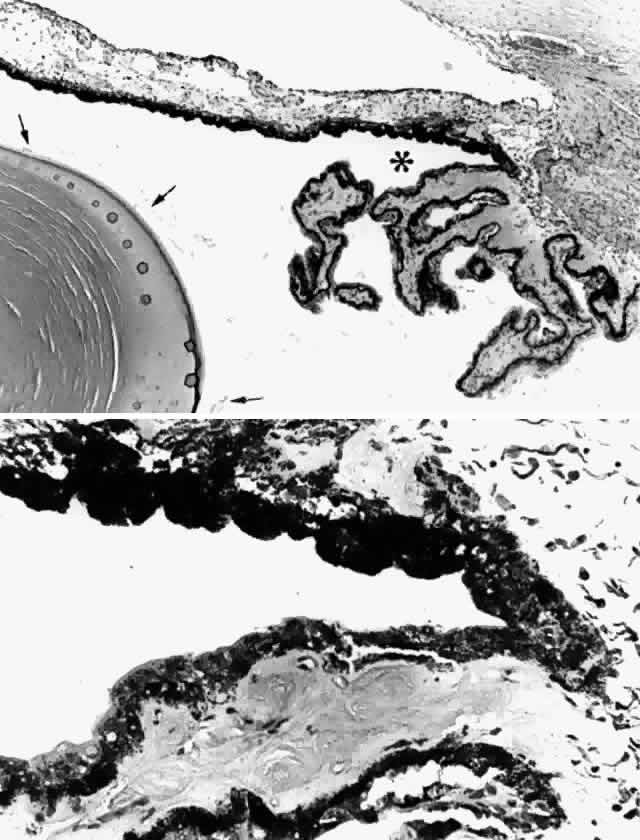

Fig. 14. Ora serrata in young adult, showing abrupt junction of ciliary nonpigmented

epithelium and sensory retina. A few hyalocytes are present in the

adjacent vitreous, and a degenerative cyst (C) is present in the peripheral

retina. (Toluidine blue, X 200) Fig. 14. Ora serrata in young adult, showing abrupt junction of ciliary nonpigmented

epithelium and sensory retina. A few hyalocytes are present in the

adjacent vitreous, and a degenerative cyst (C) is present in the peripheral

retina. (Toluidine blue, X 200)